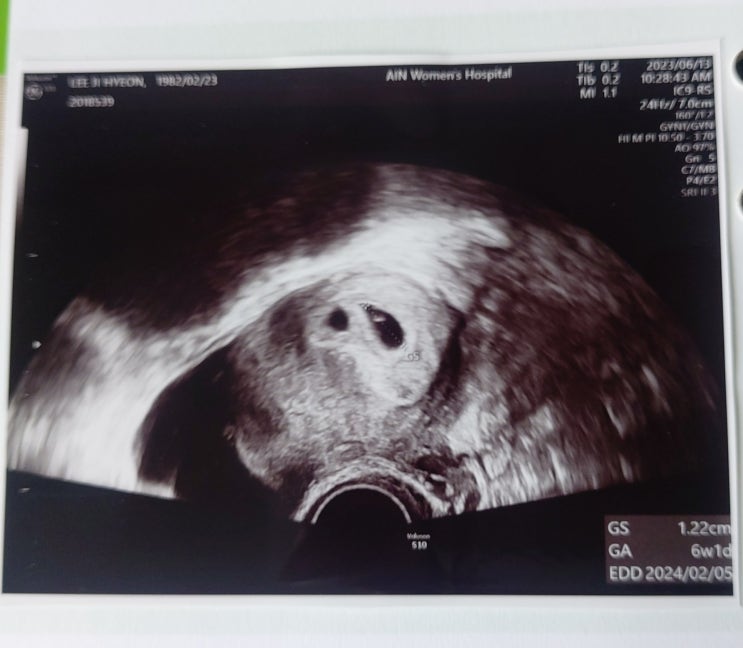

[시험관시술]37일차 아기집 확인하는 날

2023년 06월 13일 병원비 : 22,400(지원금 20,160원 / 개인부담금 2,240원) 약제비 : 없음 ==&...